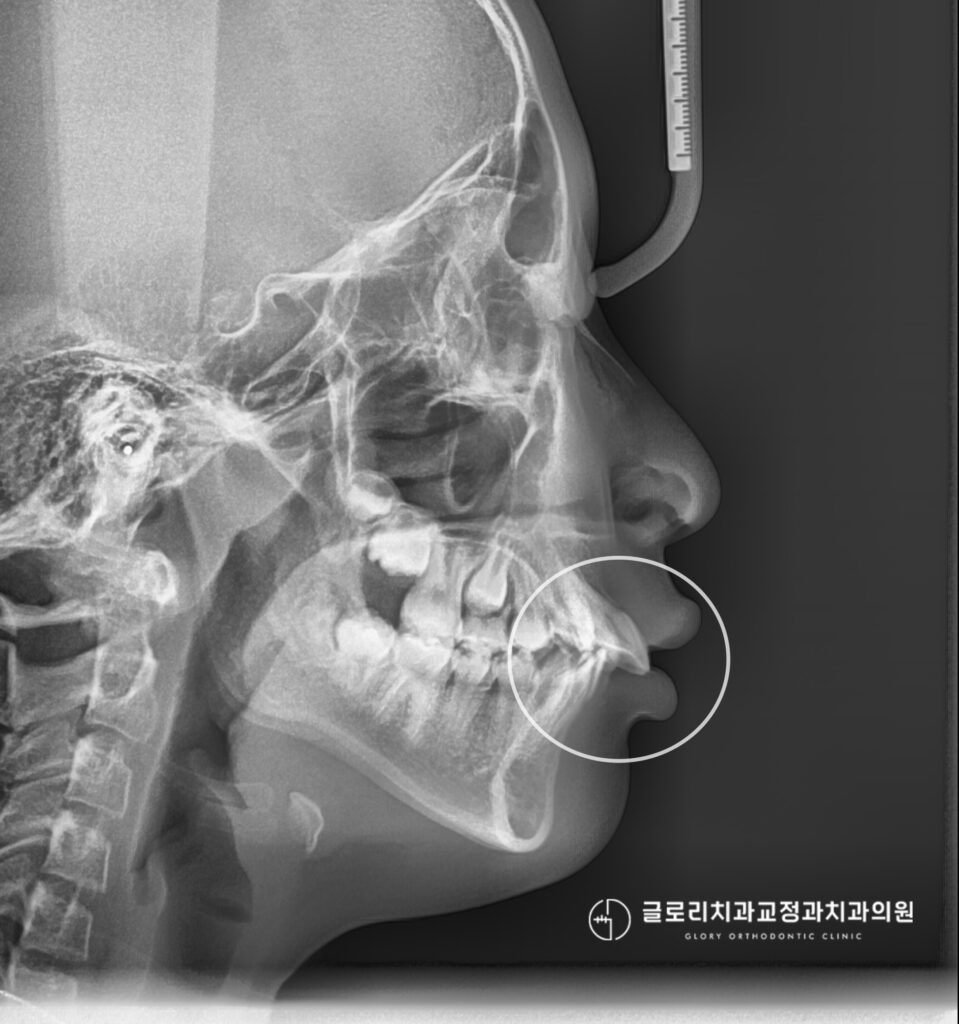

세팔로 방사선 사잔을 통해 분석해본 결과, 현재 전후방적으로 위턱에 비해 아래턱이 상대적으로 작고

후방에 위치한 골격성 2급 안모로 진단되었습니다. 정상적인 교합 관계라면 상하악이 조화롭게 맞물려야 되지만,

이번 케이스의 경우 하악의 저성장으로 돌출되어 보이는 양상이 나타났다 판단됩니다.

이어서 치열도 살펴볼 수 있는데 윗니가 아랫니를 과도하게 덮고있는

과개교합 양상을 보이고 있고 앞쪽으로 경사져 있어 이로 인해 돌출이 더욱 두드러져 보입니다.